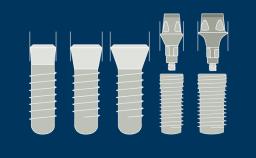

Este módulo concentra-se no conceito de integração de implantes dentários nos tecidos moles e duros da cavidade oral. A integração no osso é chamada de osseointegração e esse fenômeno, em específico, revolucionou essencialmente a maneira como os dentes ausentes podem ser substituídos. A osseointegração tem implicações clínicas para todas especialidades de dentistas envolvidas, bem como para pacientes com qualquer ausência de elementos dentários. Implantes são ancorados no tecido ósseo e penetram no tecido mole. É essencial entender os tecidos moles e duros ao redor de reabilitações sobre implantes dentários, pois somente isso permite reabilitações ideais.

- relacionar efeitos de diferentes conexões implante/pilar nos tecidos marginais